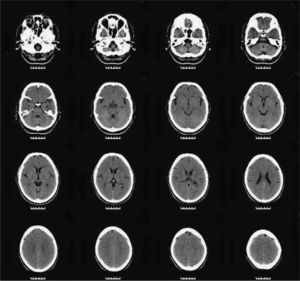

We asked for a magnetic resonance (MR) and a SPECT as complementary tests to see if there were anatomical brain findings of Crow's Type II schizophrenia.15 The patient had already had a brain MR in 2005, without finding any significant alterations. The 2010 MR revealed the presence of slight, predominantly frontal cerebral atrophy (Fig. 3), while a bilateral temporal hypoperfusion was observed in the SPECT (Fig. 4).

It was only after many years of illness, as a conclusion to the patient's evolution, the results from the psychometric tests described above and the findings from the 2 neuroimaging tests helped us to reach the conviction that everything supported the diagnosis of simple schizophrenia.17

Although not always, in various studies on neuromorphological anomalies of patients diagnosed with simple schizophrenia, there are anomalies typical of other schizophrenia subtypes, such as greater ventricular and subarachnoid space volumes, as well as further alterations in brain development.23–25 Studies on visual evoked potentials show alterations in various subtypes of patients with schizophrenia, including those who received the diagnosis of simple schizophrenia.26 Functional neuroimaging tests like the SPECT can demonstrate a deficit of perfusion in the frontal regions, associated with aspects of schizophrenia such as chronicity, presence of a negative clinical syndrome and cognitive deterioration17. This hypoperfusion of the prefrontal grey matter has also been found in more recent studies, such as Suzuki's.27

This is a disorder that, psychopathologically speaking, can present with a low symptom profile (in the case we describe, the personality test results oscillated from very pathological, in 2005, and normal, in 2010). Consequently, using tests for functional and neuropsychological deterioration, as well as functional neuroimaging tests, can be very useful for diagnosing it.18